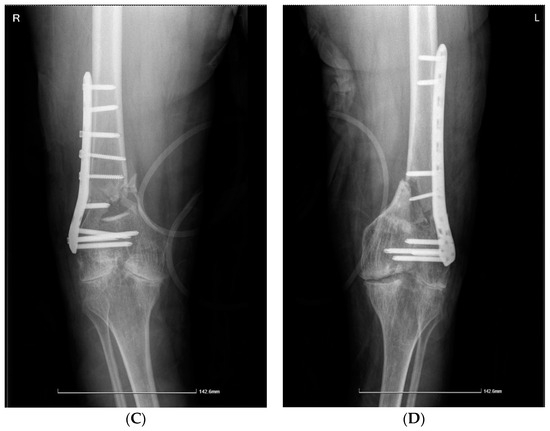

Case 2. A 39-year-old patient with severe haemophilia A, haemophilic arthropathies, and chronic viral hepatitis C, but no other comorbidities, was brought to the Emergency Unit after a car accident with acute pain and complete functional impotence of both legs. Upon examination, it was found that the patient had a bilateral femoral supracondylar fracture (Figure 2A,B). The patient underwent surgical intervention, specifically an open reduction and osteosynthesis with plates and screws on both legs (Figure 2C,D), while being treated with an extended half-life (EHL) FVIII concentrate to prevent and control bleeding. The total EHL FVIII required for the surgery and recovery was 63,500 IU. After three weeks of hospitalization, the patient’s condition improved, and he was discharged with the following instructions: 8–12 weeks of rest, plaster immobilization for 8–10 weeks, pain medication as needed, X-ray checkup at 4–8 weeks, and monitoring and adjustment of EHL FVIII doses. Bilateral hip-neck or femoral supracondylar fractures are rare, especially in individuals with haemophilia. A comprehensive approach and one-stage surgical intervention are recommended for these debilitating conditions despite the demanding and costly therapy involved. However, appropriate and timely management can help avoid the significantly higher costs associated with staged orthopaedic surgery.

Figure 2.

(A,B) Case 2—Computed tomography image: bilateral femoral supracondylar comminuted fracture. (C,D) Case 2—X-ray of right and left femur and knee. Open post-reduction status and internal fixation with present osteosynthesis material (plate with screws) at the level of the diaphysis and distal femoral epiphysis, following a femoral supracondylar comminuted fracture.